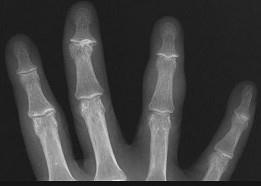

问题 女,77岁,发现右手部肿块二周,请结合影像图像提出最可能的诊断 ( )

选项 A、血管瘤 B、以上都不是 C、多发性腱鞘囊肿 D、骨囊肿 E、肌内脓肿

答案 C